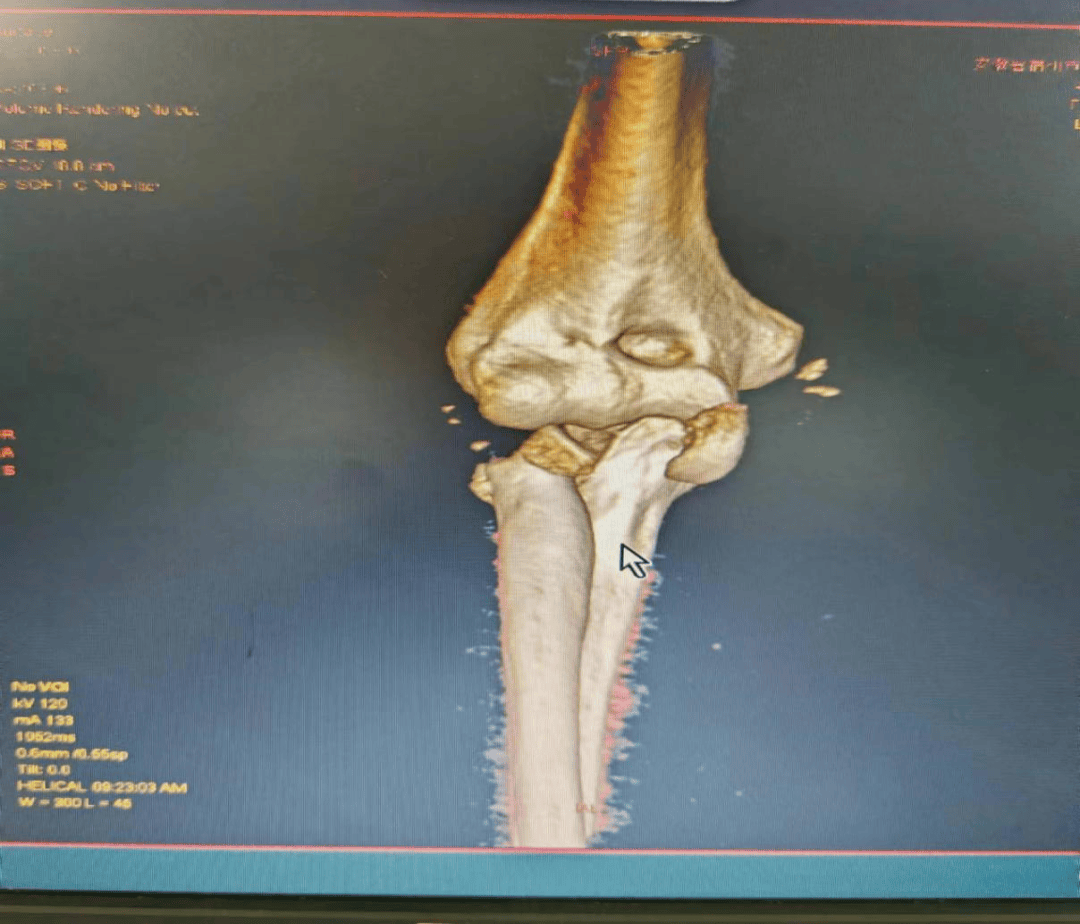

图为术后复查

近期,在安徽省第二人民医院骨科专家指导下,我院骨科诊疗水平迅猛发展,为骨科疾病患者提供更好的诊治服务。

王医师表示,桡骨头置换术的成功施行,体现了我院骨科针对复杂肘关节损伤的治疗能力和水平迈上了新的台阶。在今后的临床工作中,骨科将继续大力发展新技术,开展新项目,寻求新突破,不断提升技术水平,为全县患者提供更好地诊疗服务。